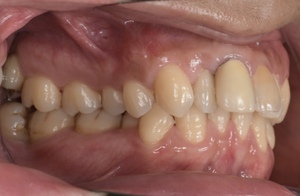

CASE 2

Before

After

| 年齢・性別 | 30代・男性 |

| 主訴 | 歯石を取りたい |

| 治療内容 | 超音波スケーラーでの歯石除去 |

| 治療期間 | 60分 |

| 治療費 | 初診料を含め約4,500円 |

| リスク・副作用 | 歯ぐきに違和感や痛みを覚える場合がある。 1週間程度、歯を磨くといつもより出血することがある。 腫れていた歯ぐきが引き締まることで歯ぐきが下がった様に見える。 歯ぐきが下がることで歯がみしやすくなることがある。 一時的に歯の動揺(ゆれ)が増す場合がある。 |